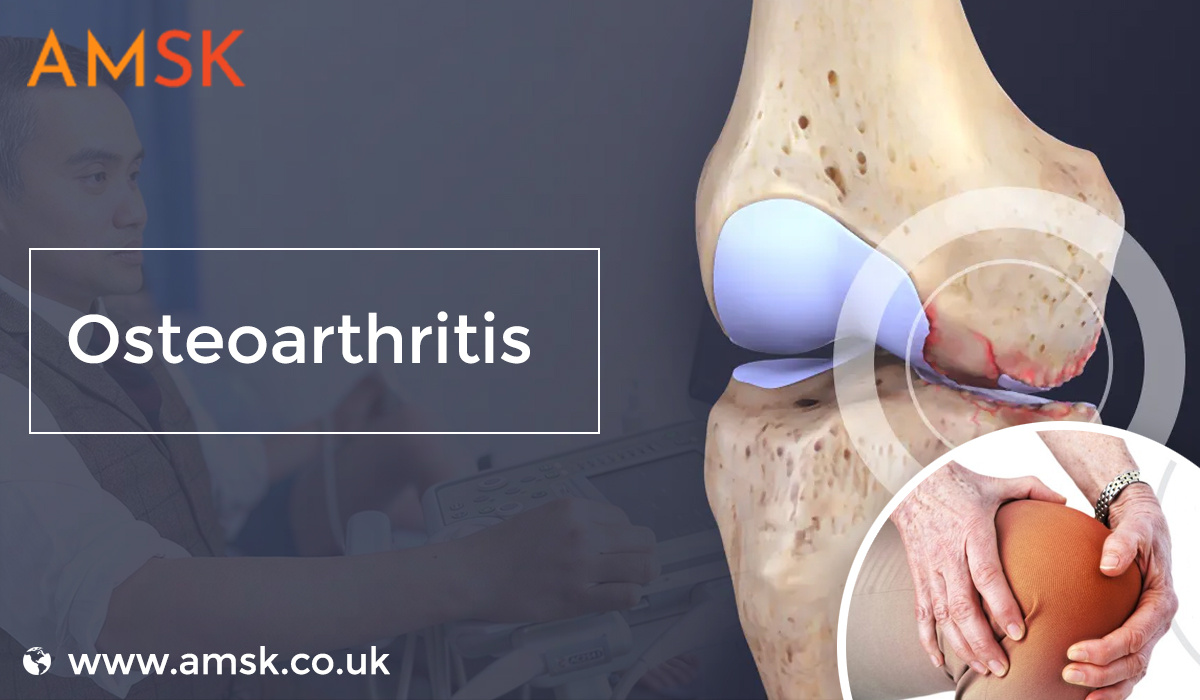

Unveiling the Knee Gel Injections Cost UK: Understanding Affordability with AMSK

In the landscape of arthritis management, knee gel injections have emerged as a promising solution for individuals seeking relief from persistent pain and discomfort. At AMSK, we recognize the importance…